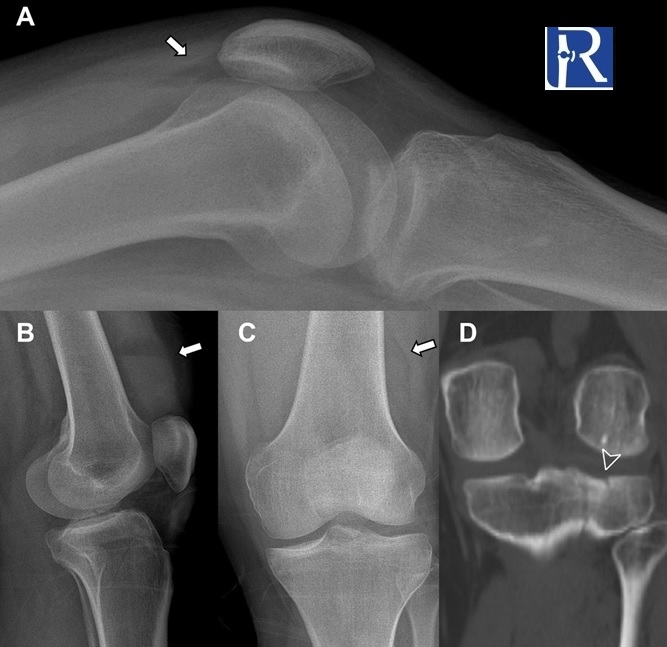

Lipohemarthrosis, characterized by the presence of a fat-fluid level, is a crucial finding in patients with acute trauma, indicating an intra-articular fracture. Our retrospective study compared the sensitivity of standing and supine lateral knee radiographs in detecting lipohemarthrosis. The results of our study revealed that standing lateral knee radiographs exhibited a higher sensitivity (95.5%) in detecting lipohemarthrosis compared to supine lateral radiographs (38.5%) (p<0.001). This finding highlights the importance of utilizing standing lateral radiographs for the diagnosis of lipohemarthrosis, which indicates the presence of occult intra-articular fractures in patients with knee trauma. Moreover, our research demonstrated good-excellent interobserver agreement in the detection of lipohemarthrosis, further validating the reliability of this technique.

These findings highlight the significance of our study and its implications for clinical practice. Our results suggest that knee trauma patients, whenever feasible, should be evaluated using standing lateral radiographs to enhance the detection of lipohemarthrosis. By leveraging this technique, clinicians can improve diagnostic accuracy and promptly identify intra-articular fractures, enabling appropriate management and treatment decisions for patients with knee trauma.